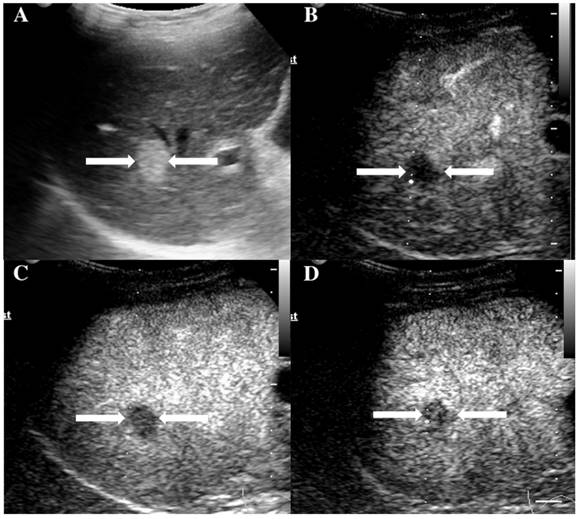

At last, of the 37 observations classified as LR-5, 33 (89.19%) were pathologically confirmed as malignant including 1 ICC (2.7%) and 32 HCC (86.49%). The typical ultrasound images are shown in Figure 1. However, 4 lesions (10.81 %) were histologically proved to be benign, 3 regenerative nodule (8.11%) (Figure 2) and 1 focal nodular hyperplasia (2.7%). With respect to the 8 LR-4 observations, 4 cases (50%) turned out to be HCCs (Figure 3). Angioma, focal nodular hyperplasia (Figure 4) and regenerative nodule accounts for 12.5% (1/8), 12.5% (1/8) and 25% (2/8) respectively. Nine observations categorized as LR-M consist of 7 (77.78%) HCC (Figure 5), 1 (11.11%) ICC and 1 (11.11%) RLH, based on pathological findings. The correct diagnoses of HCC, ICC and benign lesions were used to measure diagnostic accuracy for LI-RADS-CEUS. An example of successful categorization of HCC as LR-3 was shown in Figure 6. For the diagnosis of HCC, the overall diagnostic accuracy of LR-5 was 86.49 % (32/37) and that of LR-4 was 50% (4/8). However, the diagnostic accuracy of LR-M was only 11.11% in the retrospective study (Table 3).

Figure 1

The assigned LI-RADS category of this patient was LR-5. Hepatocellular carcinoma (HCC) was confirmed by histopathology. A. Conventional B-mode image showed a hypoechoic nodule (arrows) of about 1.8cm on the right hepatic lobe of a 52-year-old male patient. B. CEUS showed hyperenhancement (arrows) in arterial phase. C. CEUS showed hypoenhancement (arrows) in the late phase.